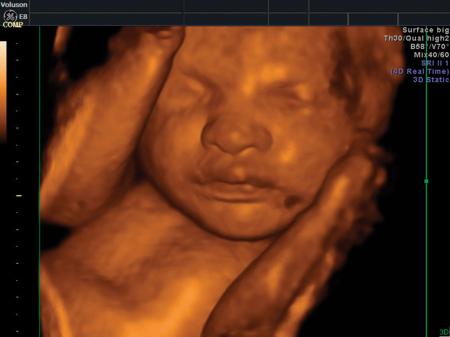

La ecografía 4D HD/5D consiste en la adquisición y presentación continúa de volúmenes. La denominación de la técnica obedece a que hay cuatro dimensiones involucradas: ancho, largo, profundidad y tiempo.

Si bien la Ecografía 4D HD/5D puede realizarse en cualquier etapa del embarazo, recomendamos realizarla entre las semanas 24 a 32 de gestación ya que se pueden observar rasgos bien definidos en el bebe.

Fotografías de ecografías 4D HD/5D

Haga click sobre las imágenes para ampliar